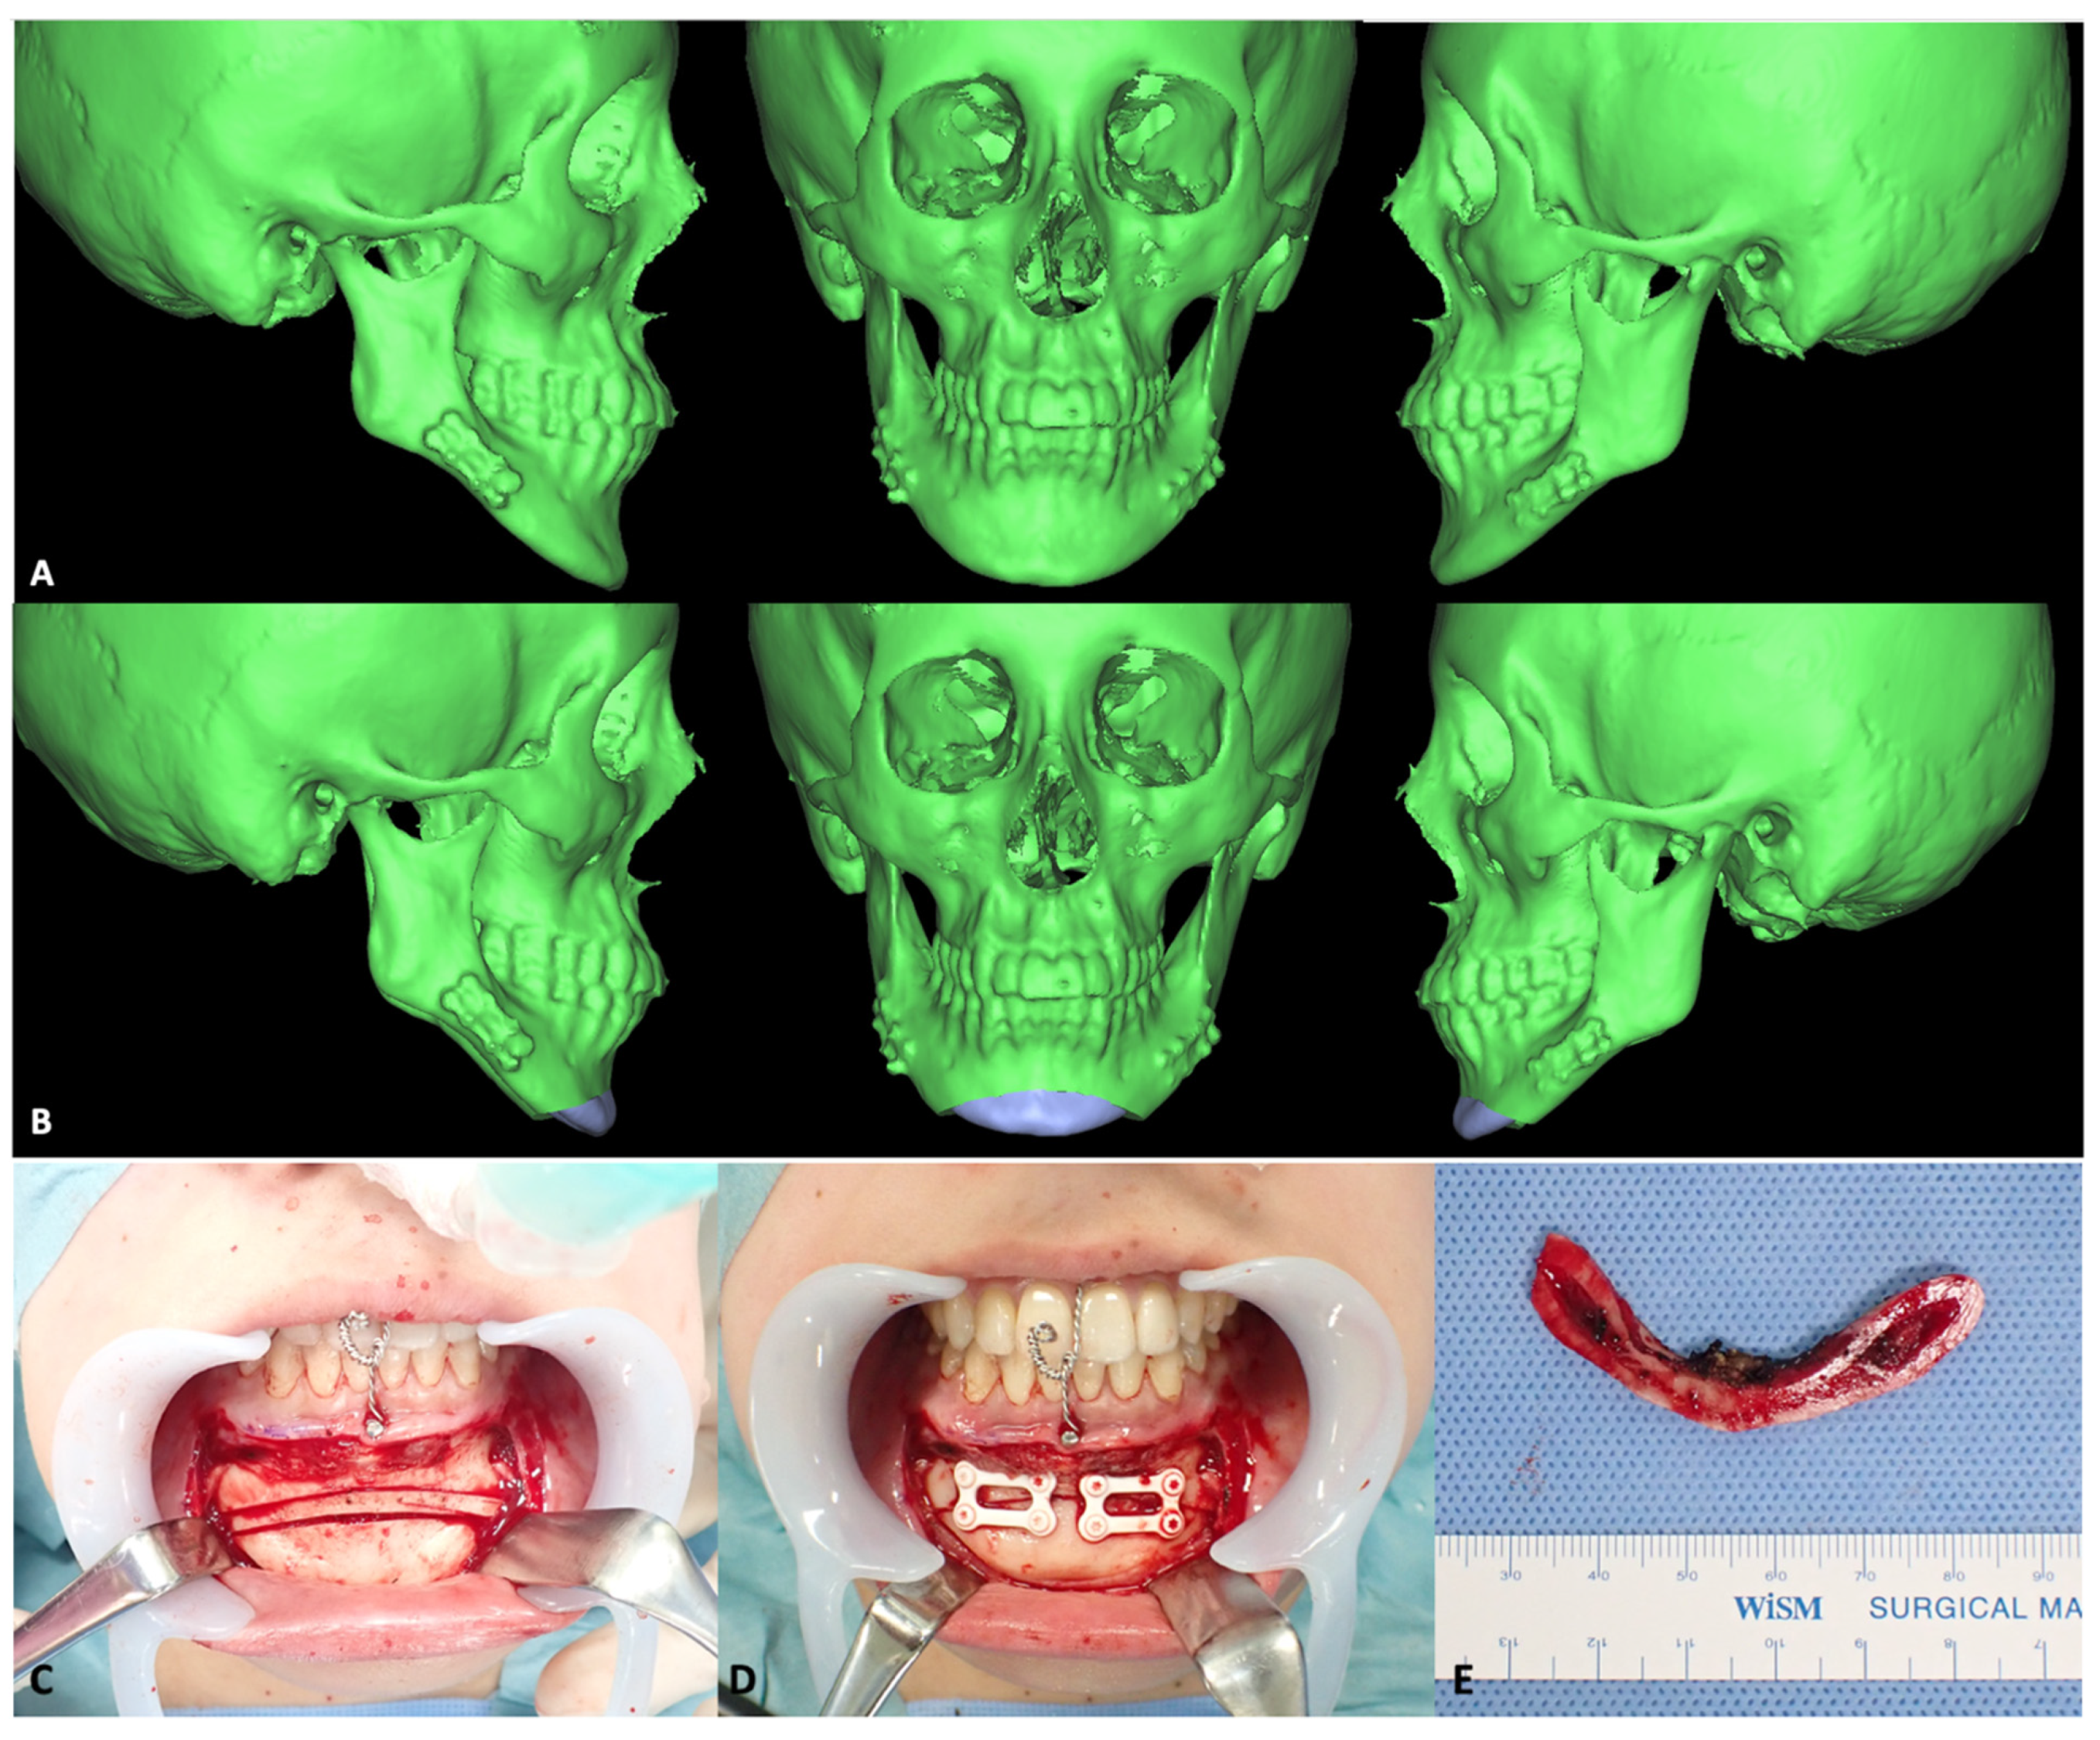

3.2.2. Mandibular Osteotomies

- Ueki, K.; Okabe, K.; Miyazaki, M.; Mukozawa, A.; Moroi, A.; Marukawa, K.; Nakagawa, K.; Yamamoto, E. Skeletal stability after mandibular setback surgery: Comparisons among unsintered hydroxyapatite/poly-L-lactic acid plate, poly-L-lactic acid plate, and titanium plate. J. Oral Maxillofac. Surg. 2011, 69, 1464–1468. [Google Scholar] [CrossRef] [PubMed] [Green Version]

- Ueki, K.; Okabe, K.; Marukawa, K.; Mukozawa, A.; Moroi, A.; Miyazaki, M.; Sotobori, M.; Ishihara, Y.; Yoshizawa, K.; Ooi, K. Skeletal stability after mandibular setback surgery: Comparison between the hybrid technique for fixation and the conventional plate fixation using an absorbable plate and screws. J. Cranio-Maxillofacial Surg. 2014, 42, 351–355. [Google Scholar] [CrossRef] [PubMed]

- Ueki, K.; Moroi, A.; Yoshizawa, K.; Hotta, A.; Tsutsui, T.; Fukaya, K.; Hiraide, R.; Takayama, A.; Tsunoda, T.; Saito, Y. Comparison of skeletal stability after sagittal split ramus osteotomy among mono-cortical plate fixation, bi-cortical plate fixation, and hybrid fixation using absorbable plates and screws. J. Cranio-Maxillofacial Surg. 2017, 45, 178–182. [Google Scholar] [CrossRef]

- Sukegawa, S.; Kanno, T.; Manabe, Y.; Matsumoto, K.; Sukegawa-Takahashi, Y.; Masui, M.; Furuki, Y. Biomechanical Loading Evaluation of Unsintered Hydroxyapatite/poly-l-lactide Plate System in Bilateral Sagittal Split Ramus Osteotomy. Materials 2017, 10, 764. [Google Scholar] [CrossRef] [Green Version]

- Park, Y.-W.; Kang, H.-S.; Lee, J.-H. Comparative study on long-term stability in mandibular sagittal split ramus osteotomy: Hydroxyapatite/poly-l-lactide mesh versus titanium miniplate. Maxillofac. Plast. Reconstr. Surg. 2019, 41, 8. [Google Scholar] [CrossRef] [PubMed] [Green Version]